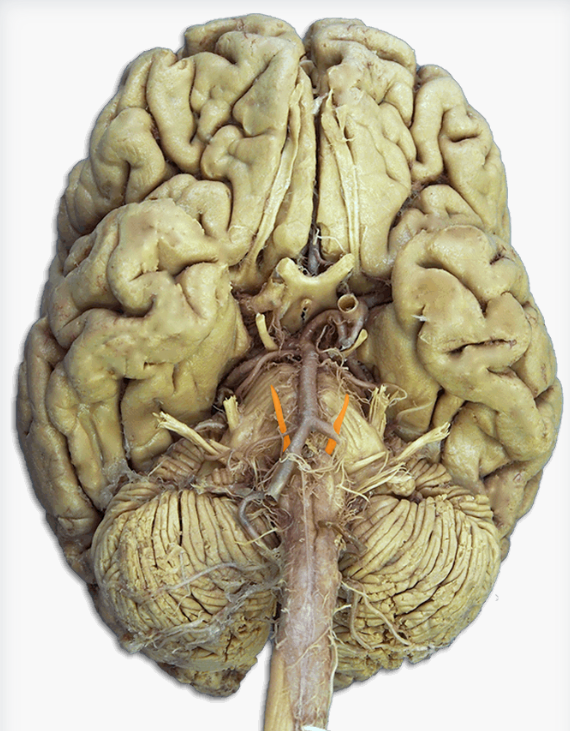

Label this cerebral artery

Basilar artery

Label this cerebral artery

Anterior communicating artery

Label this cerebral artery

Middle Cerebral Artery

Label this cerebral artery

Posterior Cerebral Artery

Label this cranial nerve

Olfactory (CN I) nerve

Label this cranial nerve

Optic (CN II) nerve

Label this cranial nerve

Oculomotor (CN III) nerve

Label this cranial nerve

Trochlear (CN IV) nerve

Label this cranial nerve

Trigeminal (CN V) nerve

Label this cranial nerve

Abducens (CN VI) nerve

Label this cranial nerve

Facial (CN VII) nerve

Label this cranial nerve

Vestibulocochlear (VIII) nerve

Label this cranial nerve

Glossopharyngeal (CN IX) nerve

Label this cranial nerve

Vagus (CN X) nerve

Label this cranial nerve

Accessory (CN XI) nerve

Label this cranial nerve

Hypoglossal (CN XII) nerve